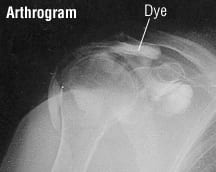

If a tear is suspected, a magnetic resonance imaging (MRI) scan can confirm the diagnosis. An alternative diagnostic test is a shoulder arthrogram. An arthrogram is an X-ray of a joint following injection of dye into the joint. Because MRIs provide excellent pictures without putting a needle into a joint, arthrograms are done less frequently today.